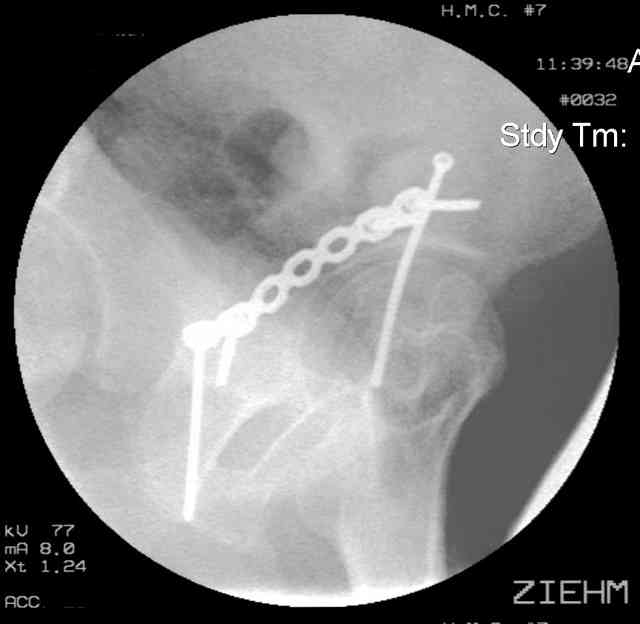

You can adjust the quadrilateral surface contact point as needed to get the fracture to reduce...we plan this based on the fracture orientation on the preop CT scan images...the clamp should be balanced to avoid over compressing one portion and distracting the other limb. Go back to and you¹ll see on the injury CT where the clamp tines need to be.

Prone

Here's a pic from the foot of the bed and you can see the clamp in the wound and the knee is extended so he must've had a tight rectus. The C-arm is rolled back to an obturator oblique image to reveal the anterior column...we put a slight outlet tilt to combine the images and give a better view of the anterior column...we can see the posterior column limb reduction in the wound, we can palpate the quadrilateral surface limb, and the image demonstrates the anterior column portion...you can adjust the tilt and rotation to image tangentially to the fracture plane if you'd like. We've inserted a 2mm K wire to site the starting point and aim/orientation for the drill and screw

Prone Imaging

same image, just another look.

Prone Inlet

OK, now we're inserting the drill percutaneosuy using a sleeve. This fluoro shot is not for this patient (notice no clamp) but I was too lazy to go searching the PACS for one with the clamp on, so pretend...I'll save the next ones and send along...the imaging is the same and the clamp doesn't obstruct imaging other than very rarely...you can always tilt the C-arm a bit to clear it if the clamp obstructs the exact spot that you'd like to see. We'll assume that everyone knows the safe zone for a medullary ramus screw. Use a calibrated drill and sleeve of known length to simplify your life...or use Alex's fancy cannulated screws...I like 3.5mm screws because the oscillating 2.5mm drill bounces and remains intraosseus when it oscillates and contacts endosteal cortical ramus... so will the screw, and like a long bent screw IF the fracture is clamped... if unclamped, when the screw contacts the endosteum, it pushes the reduction apart instead of bouncing. The big 7mm cannulated screws fit few patients and extrude...we very rarely use them any more...you'll see an old one later.

Prone Obturator-Outlet

Screw insertion using the obturator-outlet combination image.

12.Prone Obturator-Outlet

Same with a contoured pelvic reconstruction plate applied and tensioned.

Prone Iliac Oblique

The other oblique reveals the extra-articular implants.... you know the AC screw is extra-articular from the other views.

Routine Fixation

AC Screw

PC Neutr Plate

Others

The unstable caudal segment is secured by the lower 2 plate screws and the AC medullary screw... always assure that your fixation is sufficient to defeat the instability... part of your prop plan... but assure it before you close... it¹s your last chance... you shouldn't have to be pushing on the hip in contorted ways to determine your fixation stability...you can if that makes you 'comfortable'.